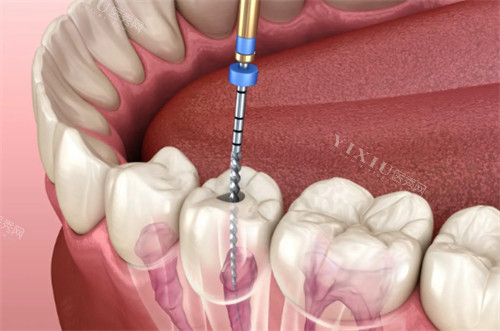

根管治疗是目前治疗牙髓炎更常用且有效的方法。其原理是通过清除根管内的炎症牙髓和坏死物质,进行适当的消毒,充填根管,以去除根管内容物对根尖周围组织的不良刺激,防止发生根尖周病变或促进根尖周病变的愈合。

根管治疗的步骤

开髓引流:在局部麻醉下,医生会打开牙髓腔,释放牙髓腔内的压力,降低疼痛。

根管预备:使用特殊的器械清理和扩大根管,去除根管内的感染物质。

根管消毒:在根管内放置消毒药物,进一步杀灭细菌。

根管充填:用根管充填材料将根管严密充填,防止细菌再次侵入。